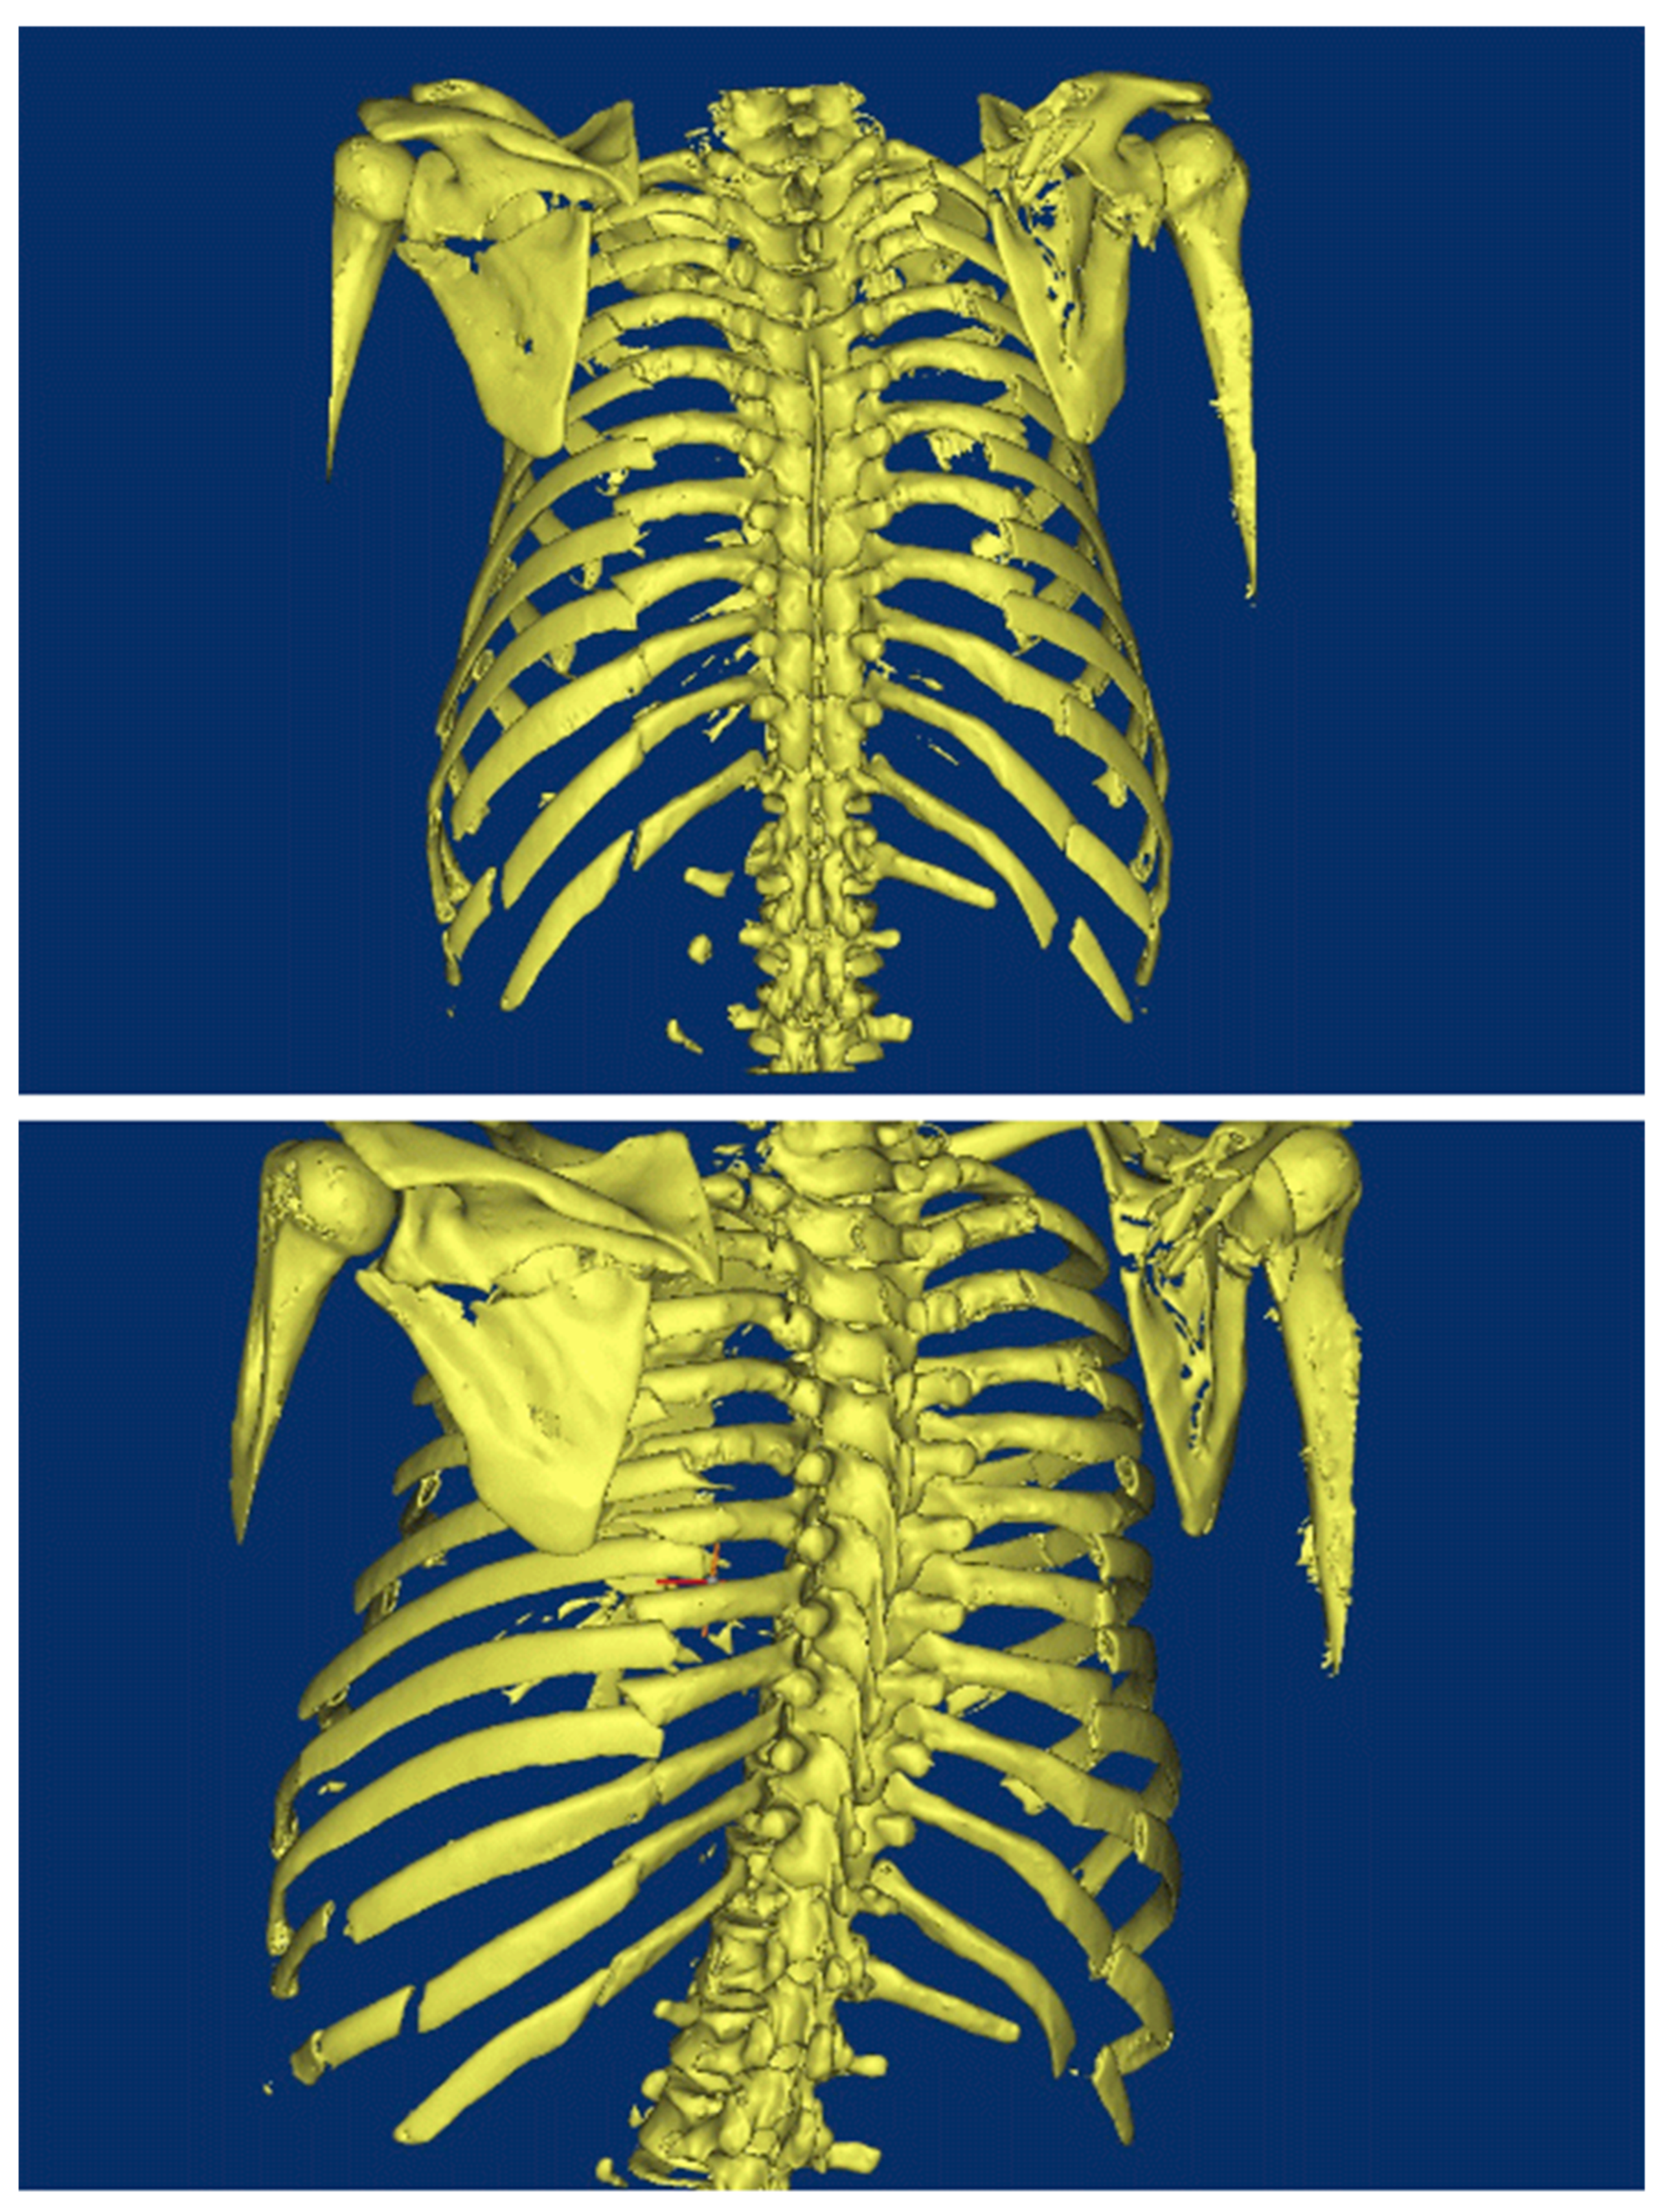

2. Background of Damaged Human Body

3. Reconstruction of the Damaged Human Model

4.1. Pre-Processing of Computational Numerical Analysis